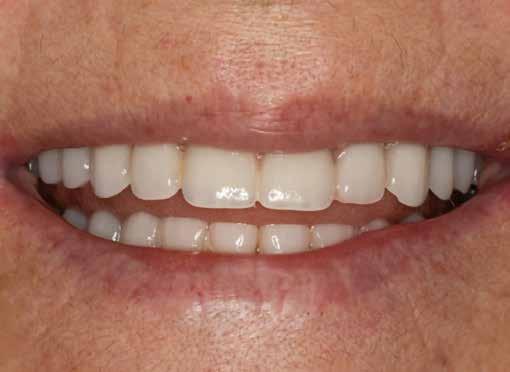

A 64 éves kaukázusi nőpáciens 2004 óta áll gondozásunk alatt, az alsó fogíven sikeres All-on-4 kezelésen van túl (1. ábra). Felső állcsontja több mint harminc éve fogatlan, de erősen motivált a sebészi rehabilitációra. A páciens elsődleges célja egy fix fogpótlás volt, amely helyreállítja a rágófunkciót és az esztétikus megjelenést (2. ábra).

7. ábra: Extraorális felvétel a mosolyról az ideiglenes rögzített fogpótlás átadását követően.

8. ábra: Intraorális felvétel az ideiglenes rögzített fogpótlás okkluzális felszínéről, átadást követően.